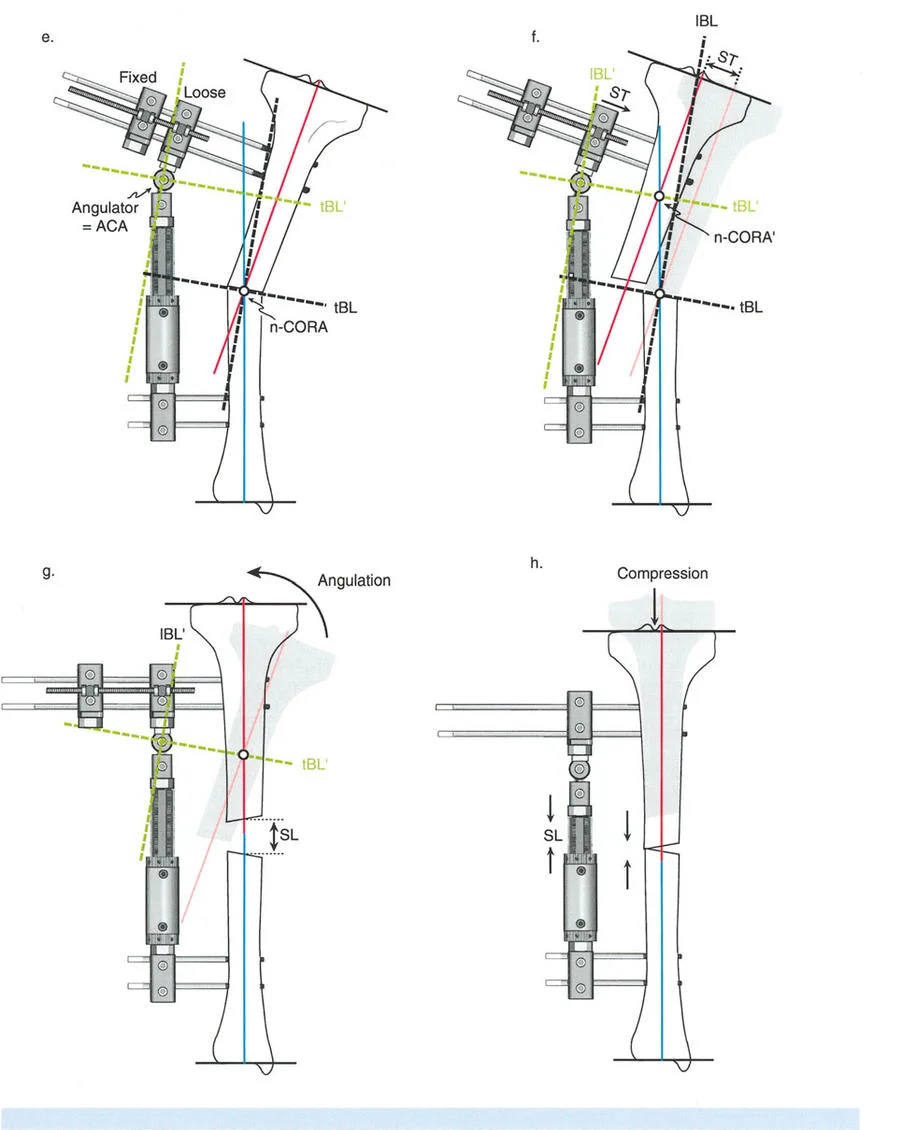

المفصلات القريبة من المفصل وقواعد قطع العظم (Osteotomy Rules)

عند التعامل مع التشوهات الواقعة بالقرب من خط المفصل - مثل التقوس الشديد في الجزء العلوي من الساق (مرض بلونت) أو التشوه الفحجي في الجزء السفلي من عظم الفخذ - يصبح وضع الجهاز مقيدًا هندسيًا. إن المتطلبات البيولوجية للحفاظ على كبسولة المفصل، وتجنب وضع الأسلاك داخل المفصل، ومنع التهاب المفاصل القيحي، غالبًا ما تجبر الجراح على وضع الحلقة المرجعية على مستوى مختلف تمامًا عن مركز دوران الانحراف (CORA) الفعلي.

تحدي مركز دوران الانحراف (CORA) القريب من المفصل

لمطابقة مفصلة المثبت الخارجي مع المستوى الدقيق لمركز دوران الانحراف (CORA)، يجب غالبًا بناء المفصلة فوق أو تحت مستوى الحلقة الفعلية. يُعرف هذا في مبادئ بالي باسم تجميع المفصلة القريبة من المفصل (juxta-articular hinge assembly).

إذا كان مركز دوران الانحراف (CORA) يقع بالقرب من خط المفصل، فإن وضع حلقة إليزاروف القياسية عند هذا المستوى بالضبط مستحيل دون انتهاك مساحة المفصل أو شد الهياكل الكبسولية الحيوية. لذلك، يتم تثبيت الحلقة المرجعية بالعظم الكثيف أو العظم الطويل المتاح، ويتم بناء آلية المفصلة باستخدام قضبان ملولبة، ولوحات توصيل، ودعامات. ثم يتم "إنزالها" (أو رفعها) لتتطابق تمامًا مع مركز دوران الانحراف (CORA) الهندسي الحقيقي.

في المنشآت القريبة من المفصل، غالبًا ما نعتمد على قاعدة قطع العظم 2. نظرًا لأنه لا يمكننا قطع العظم بأمان عند خط المفصل تمامًا (مركز دوران الانحراف CORA)، فإننا نقطع العظم في مستوى أدنى في منطقة الميتافيسيس. بعد تحقيق التصحيح الزاوي عبر المفصلات (محور تصحيح الانحراف ACA)، يتم إعادة محاذاة خطوط المحور الميكانيكي بشكل مثالي، ولكن نهايات العظم في موقع قطع العظم تتحرك بالنسبة لبعضها البعض.

نصائح جراحية للمنشآت القريبة من المفصل

| المبدأ | التطبيق السريري | تحذير / خطأ محتمل |

|---|---|---|

| التحقق من CORA | دائمًا تحقق من CORA الحقيقي في الأشعة السينية الطويلة للطرفين قبل بناء المفصلة. | الاعتماد على الأشعة السينية القصيرة للركبة سيؤدي إلى CORA غير دقيق وبالتالي سوء محاذاة. |

| ACA العمودي | تأكد من أن محور المفصلة (ACA) عمودي تمامًا على مستوى التشوه. | محور ACA مائل سيحدث تشوهًا ثانويًا غير مرغوب فيه (مثل تصحيح التقوس ولكن إحداث الانحناء الأمامي). |

| تخليص الأنسجة الرخوة | عند استخدام قاعدة قطع العظم 2، احسب الترجمة المتوقعة وتأكد من أن الأنسجة الرخوة يمكن أن تستوعبها. | عدم مراعاة الترجمة يمكن أن يتسبب في اصطدام العظم بالجلد، مما يؤدي إلى النخر. |

| تقابل الأسلاك | استخدم ما لا يقل عن سلكين زيتون متقابلين لكل قطعة إذا كنت تتجنب الدبابيس النصفية. | الأسلاك الزيتون الفردية ستسبب قصًا ودورانًا غير مرغوب فيه حول محور السلك. |